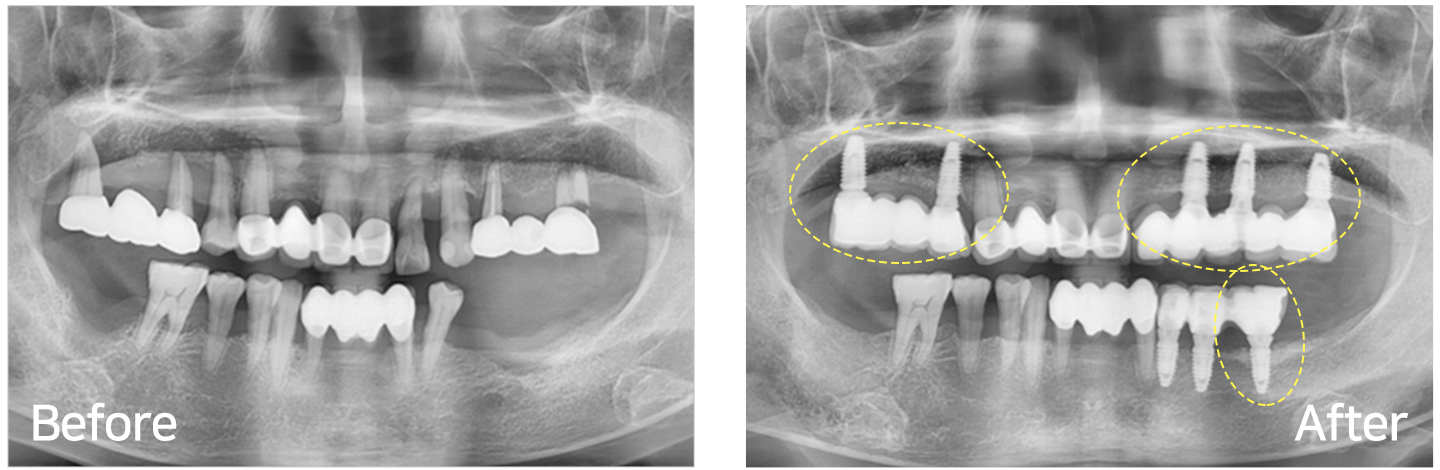

임플란트 시술 사례

IMPLANT TREATMENT CASES

※ 전신질환 및 관리 능력에 따라 임플란트 주위염 등의 부작용이 있을 수 있습니다.